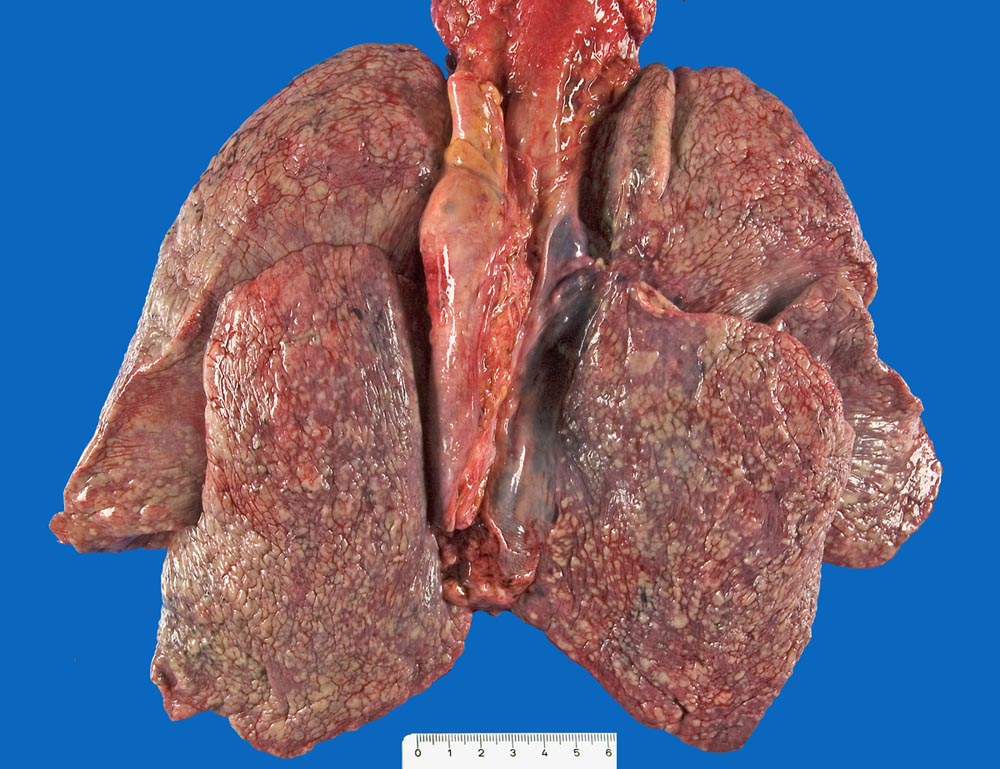

Makroskopie

Pathologischer Befund